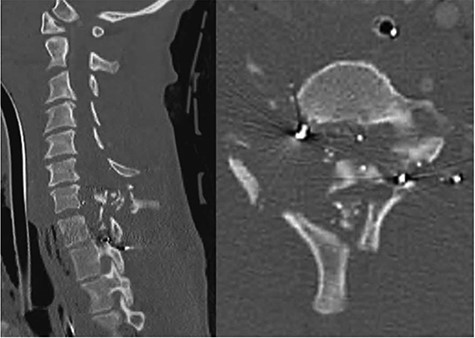

A 24-year-old African–American male presented with a gunshot wound through the left face and neck. On exam the patient was noted to be pulseless and apneic. After resuscitation, initiation of a mass transfusion protocol and return of spontaneous circulation, the patient was GCS 11 (E4V1TM6) and was noted to have no movement in any extremities. A computed tomographic (CT) cervical spine scan and CT angiography of the neck revealed a bullet trajectory through the left C2–3 facet with fractured c3 posterior elements and a bullet fragment at the C3 level, a left vertebral artery dissection, and left internal and external carotid artery transections (Fig. 1). The patient underwent an emergent tracheostomy, neck exploration, left ICA/ECA ligation and partial wound closure. This was followed by endovascular embolization of the left vertebral artery. The patient was noted to have serosanginous drainage from the neck wound consistent with a CSF leak. After an unsuccessful trail of conservative management, a lumbar drain was placed and confirmed with fluoroscopic guidance without CSF egress. A magnetic resonance imaging (MRI) scan of the cervical spine was obtained which demonstrated a pronounced CSF fistula and a complete obstruction of the CSF space at the C3–6 levels (Fig. 2).

CT angiogram of the neck demonstrates a bullet trajectory through the left C2–3 facet with fractured c3 posterior elements and bullet and bony fragments within the canal at the C3–4 level; left: sagittal view; right: axial view.